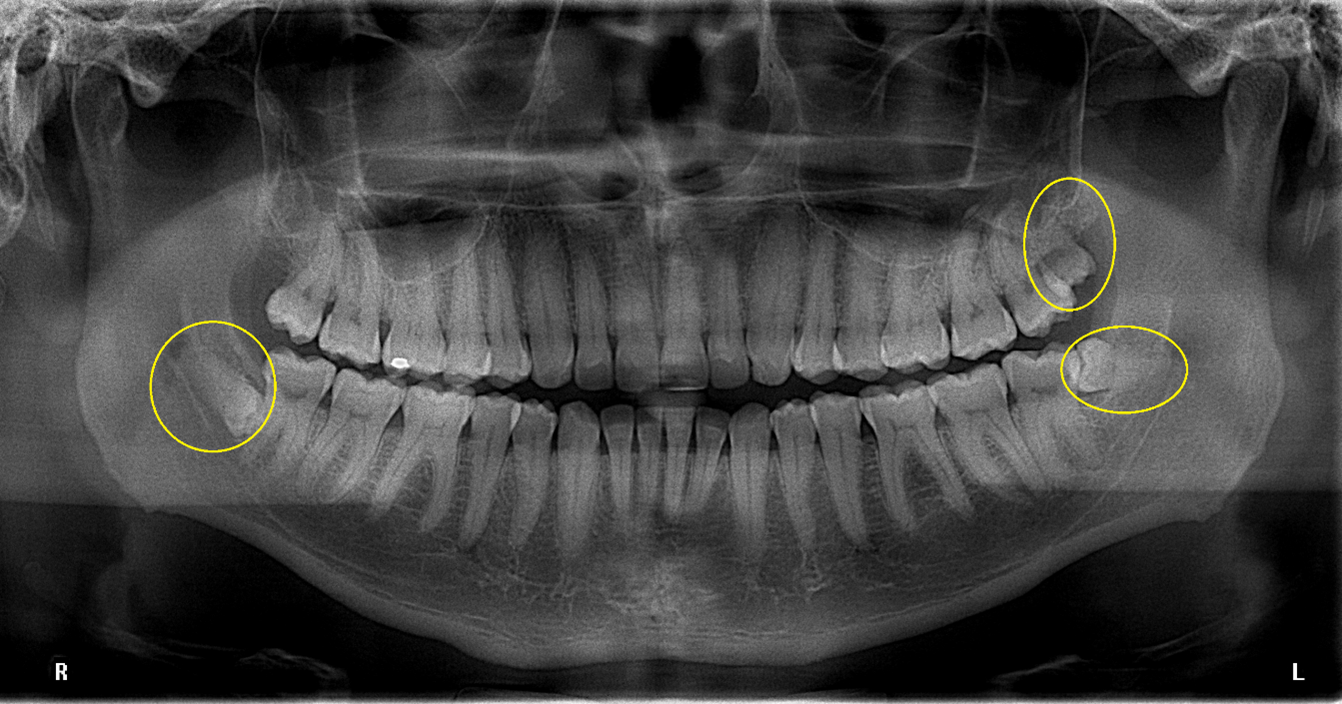

Nuestra dentadura tiene 20 piezas dentales cuando somos niños y 32 piezas en la edad adulta, incluidas las muelas del juicio. Sin embargo, algunos humanos tienen más piezas de las habituales, dientes llamados supernumerarios y patología conocida como hiperdoncia.

La presencia de los dientes supernumerarios provoca una importante alteración funcional y estética en la boca, ya que impiden a los dientes numerarios crecer con normalidad e incluso a veces provoca que no erupcionen.